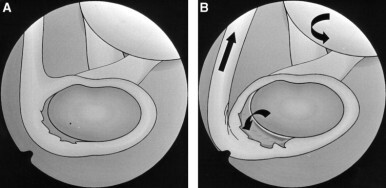

- SLAP 병변은 이 중에서 어깨 관절 와순의 손상입니다. 관절와순에서도 이두근 장두 힘줄이 관절와순과 연결된 부위와 연관되어 발생합니다.

- 손상부위는 보통 10시~2시방향에 위치합니다.

- 방카르트 병변(Bankart lesion)이나, ALPSA(anterior labroligamentous periosteal sleeve avulsion) 병변과는 다르게 어깨 불안정성과는 관련이 적습니다.